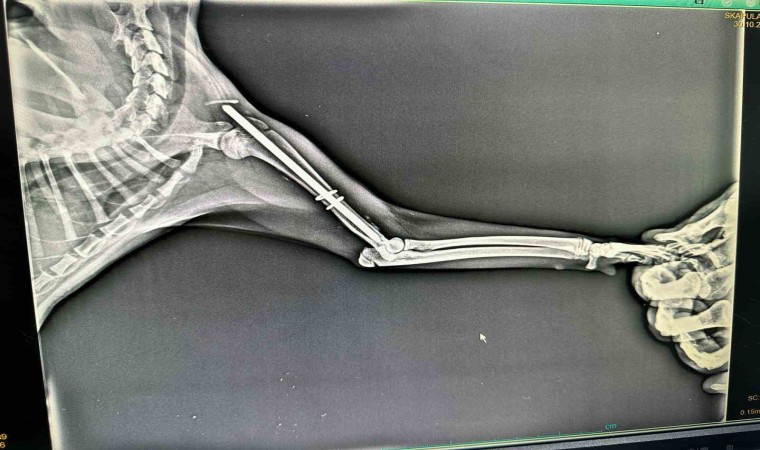

Edinilen bilgiye göre Terakki Mahallesi’nde aracın çarptığı sokak kedisini gören esnaflar kediyi alarak veteriner kliniğine getirdi. Burada yapılan ilk muayenesinde ön kol ve arka ayak kemiklerinde kırık olduğu tespit edilen kedi ameliyata alındı. Kedi ameliyatın ardından sağlığına kavuşacağı günü beklerken hayırsever vatandaşların çabası takdirle karşılandı. Kedinin ameliyat masrafları da hayırsever vatandaşlar tarafından karşılandı.